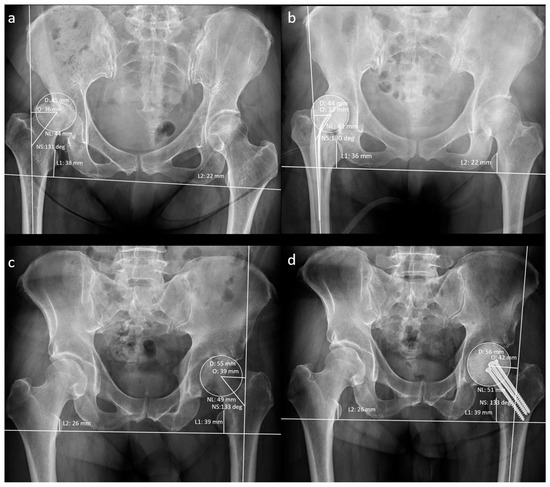

Figure 3.

Measurement of radiographic hip geometrical parameters. (a) Pre-operative n-MS hip, (b) post-operative n-MS hip, (c) pre-operative MS hip, and (d) post-operative MS hip. Δhip parameters: femoral head diameter difference (post-operative D–pre-operative D), femoral neck length difference (post-operative NL–pre-operative NL), neck–shaft angle difference (post-operative NS–preoperative NS), femoral offset difference (post-operative O–pre-operative O), and leg-length discrepancy difference (post-operative L1–L2)–(pre-operative L1–L2).